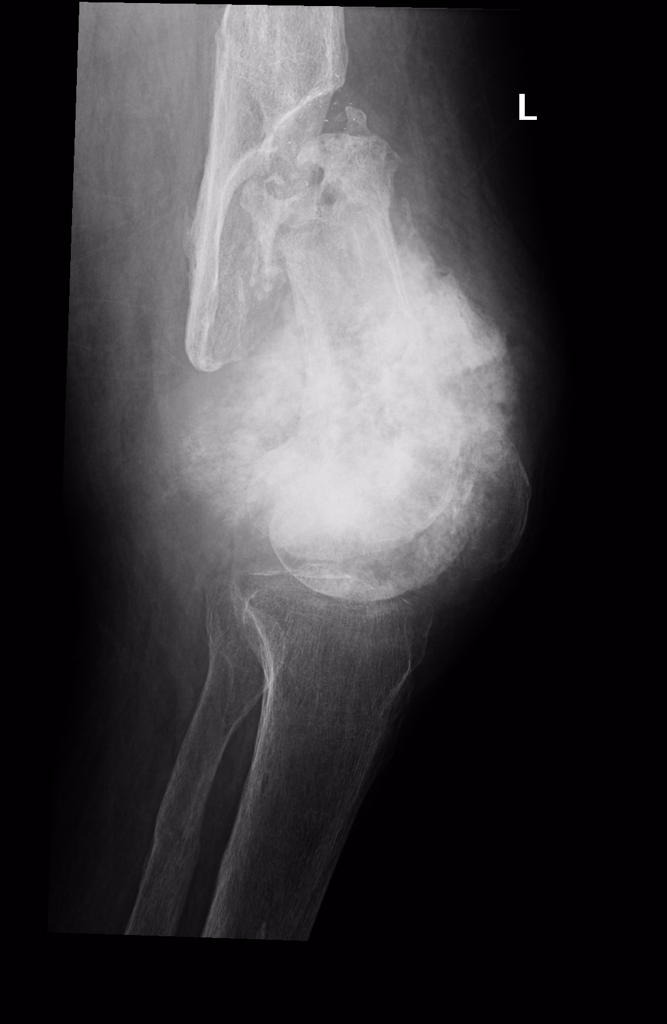

Саркома кости ноги

Саркома кости ноги 140 фото